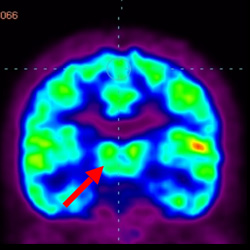

干細(xì)胞治療腦癱后改善的客觀放射學(xué)證據(jù)

細(xì)胞治療后,藍(lán)色和黑色區(qū)域減少,并且看到更活躍的區(qū)域。這表明損傷減少并改善了大腦功能。

細(xì)胞治療前 PET CT 掃描顯示神經(jīng)組織中的藍(lán)/黑色區(qū)域,表明腦癱引起的大腦損傷。

這證明細(xì)胞療法是治療腦癱兒童安全有效的方法。細(xì)胞療法可以更新大腦損傷的核心,并且可以通過 PET CT 掃描來監(jiān)測(cè)大腦的改善情況。這些細(xì)胞療法與標(biāo)準(zhǔn)治療一起促進(jìn)腦癱兒童的生長(zhǎng)和改善。